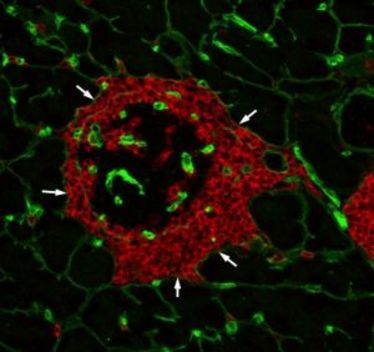

Biomolekülen auf der Spur

Biomolekülen auf der Spur